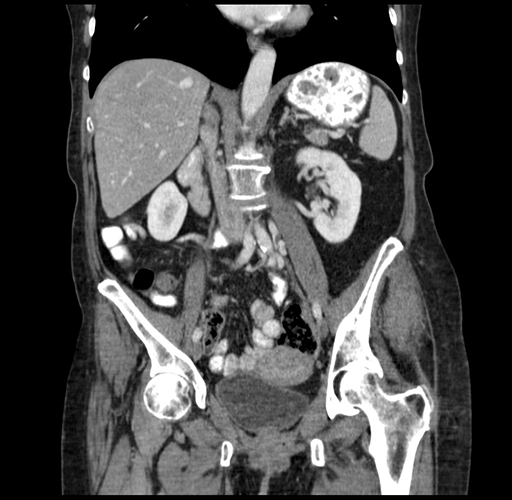

Pre-Chemo: Coronal Venous

Coronal Venous